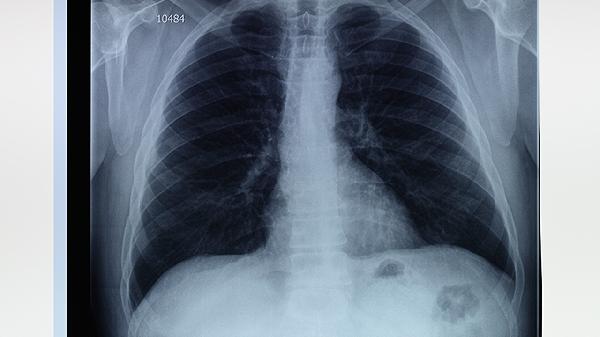

肺大泡不及时治疗可能导致气胸、感染加重、呼吸衰竭等后果。肺大泡是肺泡异常扩张形成的囊状结构,常见于慢性阻塞性肺疾病或肺气肿患者。

进行性增大的肺大泡会压迫正常肺组织,降低肺通气效率。患者出现活动后气促加重、血氧饱和度下降,最终导致慢性呼吸衰竭。需长期氧疗,严重时考虑肺减容手术。